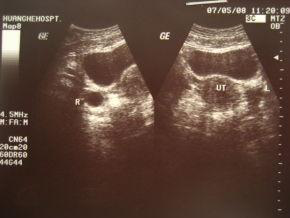

优势卵泡在所有测排卵的方法中,目前最为准确的是阴道B超监测法,它不仅可以测出两侧卵巢中是否有优势卵泡,同时还能测出优势卵泡的大小、子宫内膜的厚度等,不过这种方法一般只有患者确实需要时才使用,“比如有些宫外孕的女性,左侧输卵管已经被切掉,在这种情况下,如果她的左侧卵巢排卵,是无法怀孕的,因此可以通过做B超观察是哪一侧卵巢排卵”。 “用B超监测卵泡,最好找固定的医生监测,”当医生从某个角度观察到一个优势卵泡时,下次再从同一个角度去监测这个卵泡的发育情况会更好,“不同的医疗机构,不同的医生,判断都可能出现差异。”

监测卵泡检查方法:一般情况下,自月经周期的第8天起,每2天B超监测1次,当发现卵泡直径达17毫米时,应该改每天监测1次,当卵泡发育成熟直径达20-23毫米时,必要时每天测2次,直至排卵为止。B超探头频率3.5MHz每次监测,观察双侧卵巢大小、形态,记录卵泡数量、大小,月经第几天等。

有排卵周期的卵巢及卵泡表现。成熟卵泡的特征,B超监测最大卵泡出现在月经10-16天,卵泡直径20mm,呈圆形,壁薄,向卵巢的一侧突出,内部透声好,一般在10小时之内排卵,排卵时间在月经第12-18天内为多见,少数可在20-30天。排卵后特征:卵泡壁部分塌陷,边缘皱缩呈锯齿状,内有许多细弱光点,子宫直肠隐窝内可见液性暗区5-15mm,一般在排卵1天后消失,在此前后时间同房怀孕成功率高达90%。